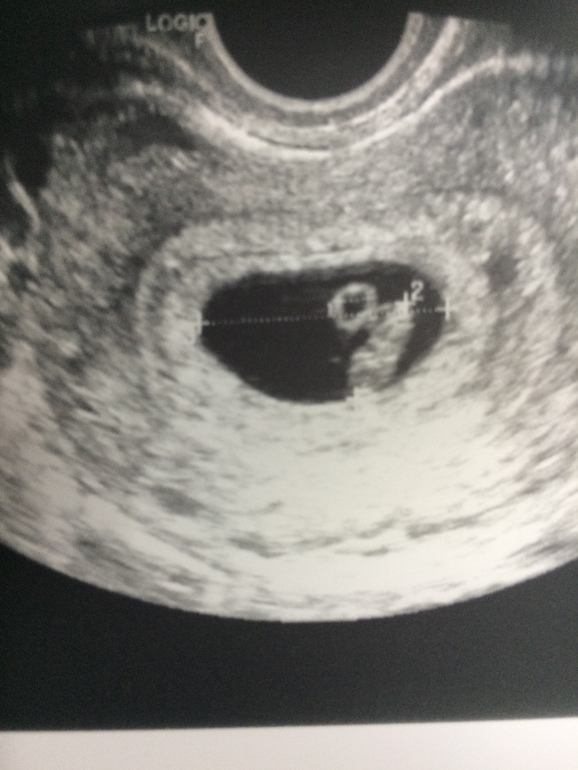

Спасибо!) я на мониторе видела как пульсирует сердечко крохотное, это что то))